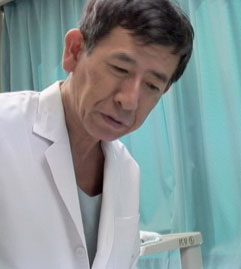

手術をするための、最後の検査だ。 |

| 約2時間半の手術で終わった。直後にレントゲンで成功を確認。 |